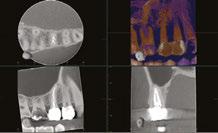

Figure 1: CBCT scan of the tooth demonstrating the radiolucent lesion surrounding the DI and extending to the apex of the central incisor Figures 2A-2D: 2A. Periapical radiograph of the dens. 2B. Hedstrom file in the invagination. 2C. The obturated enamel lining of the invagination with BC putty. 2D. Healing of the periapical lesion in the 1-year follow-up

int the C-shaped main canal. 3D.The obturated enamel of lined canals with Biodentine. The radiopacity is similar to that of dentin. 3E. Healing of the periapical lesion in the 3-year follow-up and continued root formation

Figures 3A-3E: 3A Periapical radiograph of the dens in dente. It is impossible to determine the accurate source of infection. 3B. Hedstrom file in the invagination. 3C. Files